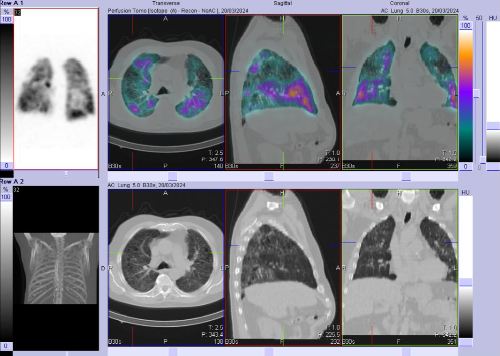

/ Obr. č. 1: Kombinovaná perfuzní a ventilační scintigrafie plic. Horní řada scintigramů – perfuze, dolní řada scintigramů – ventilace.

Na scintigramech pozorujeme vícečetné perfuzní defekty v obou plicích (v horním a dolním laloku pravé plíce a v horním a dolním laloku levé plíce). Dále je homogenní distribuce ventilace v obou plicích.

Relativní distribuce perfuze: L:P 40:60 %, relativní distribuce ventilace L:P 44:56 %.